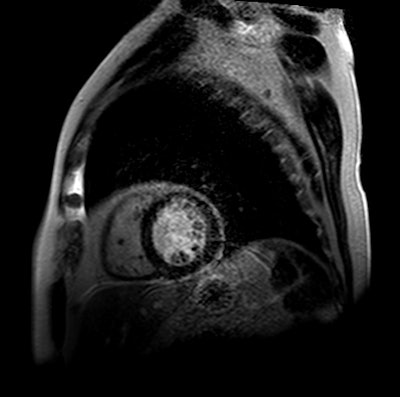

Coronary heart disease continues to be the leading cause of death and disability around the world, and MPI with SPECT is the most common test worldwide to assess myocardial ischemia. More recently, CMR has gained in popularity due to its noninvasive imaging approach and validated high diagnostic accuracy and prognostic results.

The 1,202 patients then were randomly categorized based on their treatment regimen. There were 240 subjects who followed U.K. National Institute for Health and Care Excellence (NICE) guidelines; 418 cases were directed by CMR results; and 481 individuals whose care was based on MPI findings. Efficacy of the three treatment strategies was determined on unnecessary coronary angiography result within 12 months.